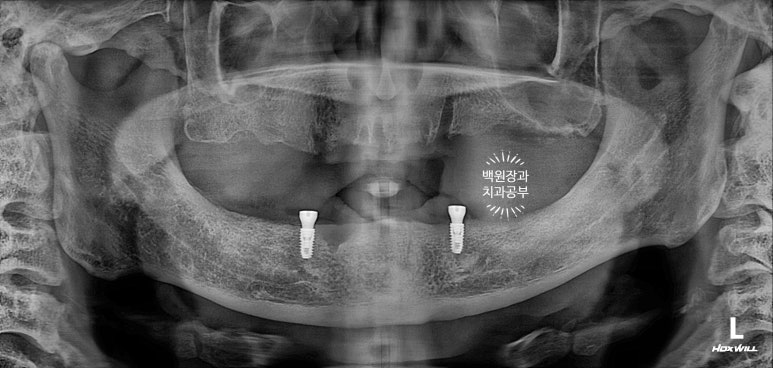

짜잔!!! 뿌리만 있던 치아들은 깔끔하게 제거되었고,

건전한 뼈가 있는 곳에 새로이 임플란트 두개를 심어드렸어요.

심고 나니 조금 더 가운데에 심었으면 좋았을텐데... 그치만 앞니 부위는 잇몸뼈의 폭이 너무나 좁았습니다.

제거된 두개의 임플란트 입니다.

오스템 임플란트의 임플란트제거 전용 키트를 사용하여 비교적 수월하게 제거할 수 있었어요.

임플란트를 심어내는 것보다도 더 어려운 것이 제거하는 것입니다.

성형외과에서도 재수술이 더 힘들다고 하잖아요~ 그와 마찬가지로 임플란트도 재수술이 훨씬 더 어렵습니다!